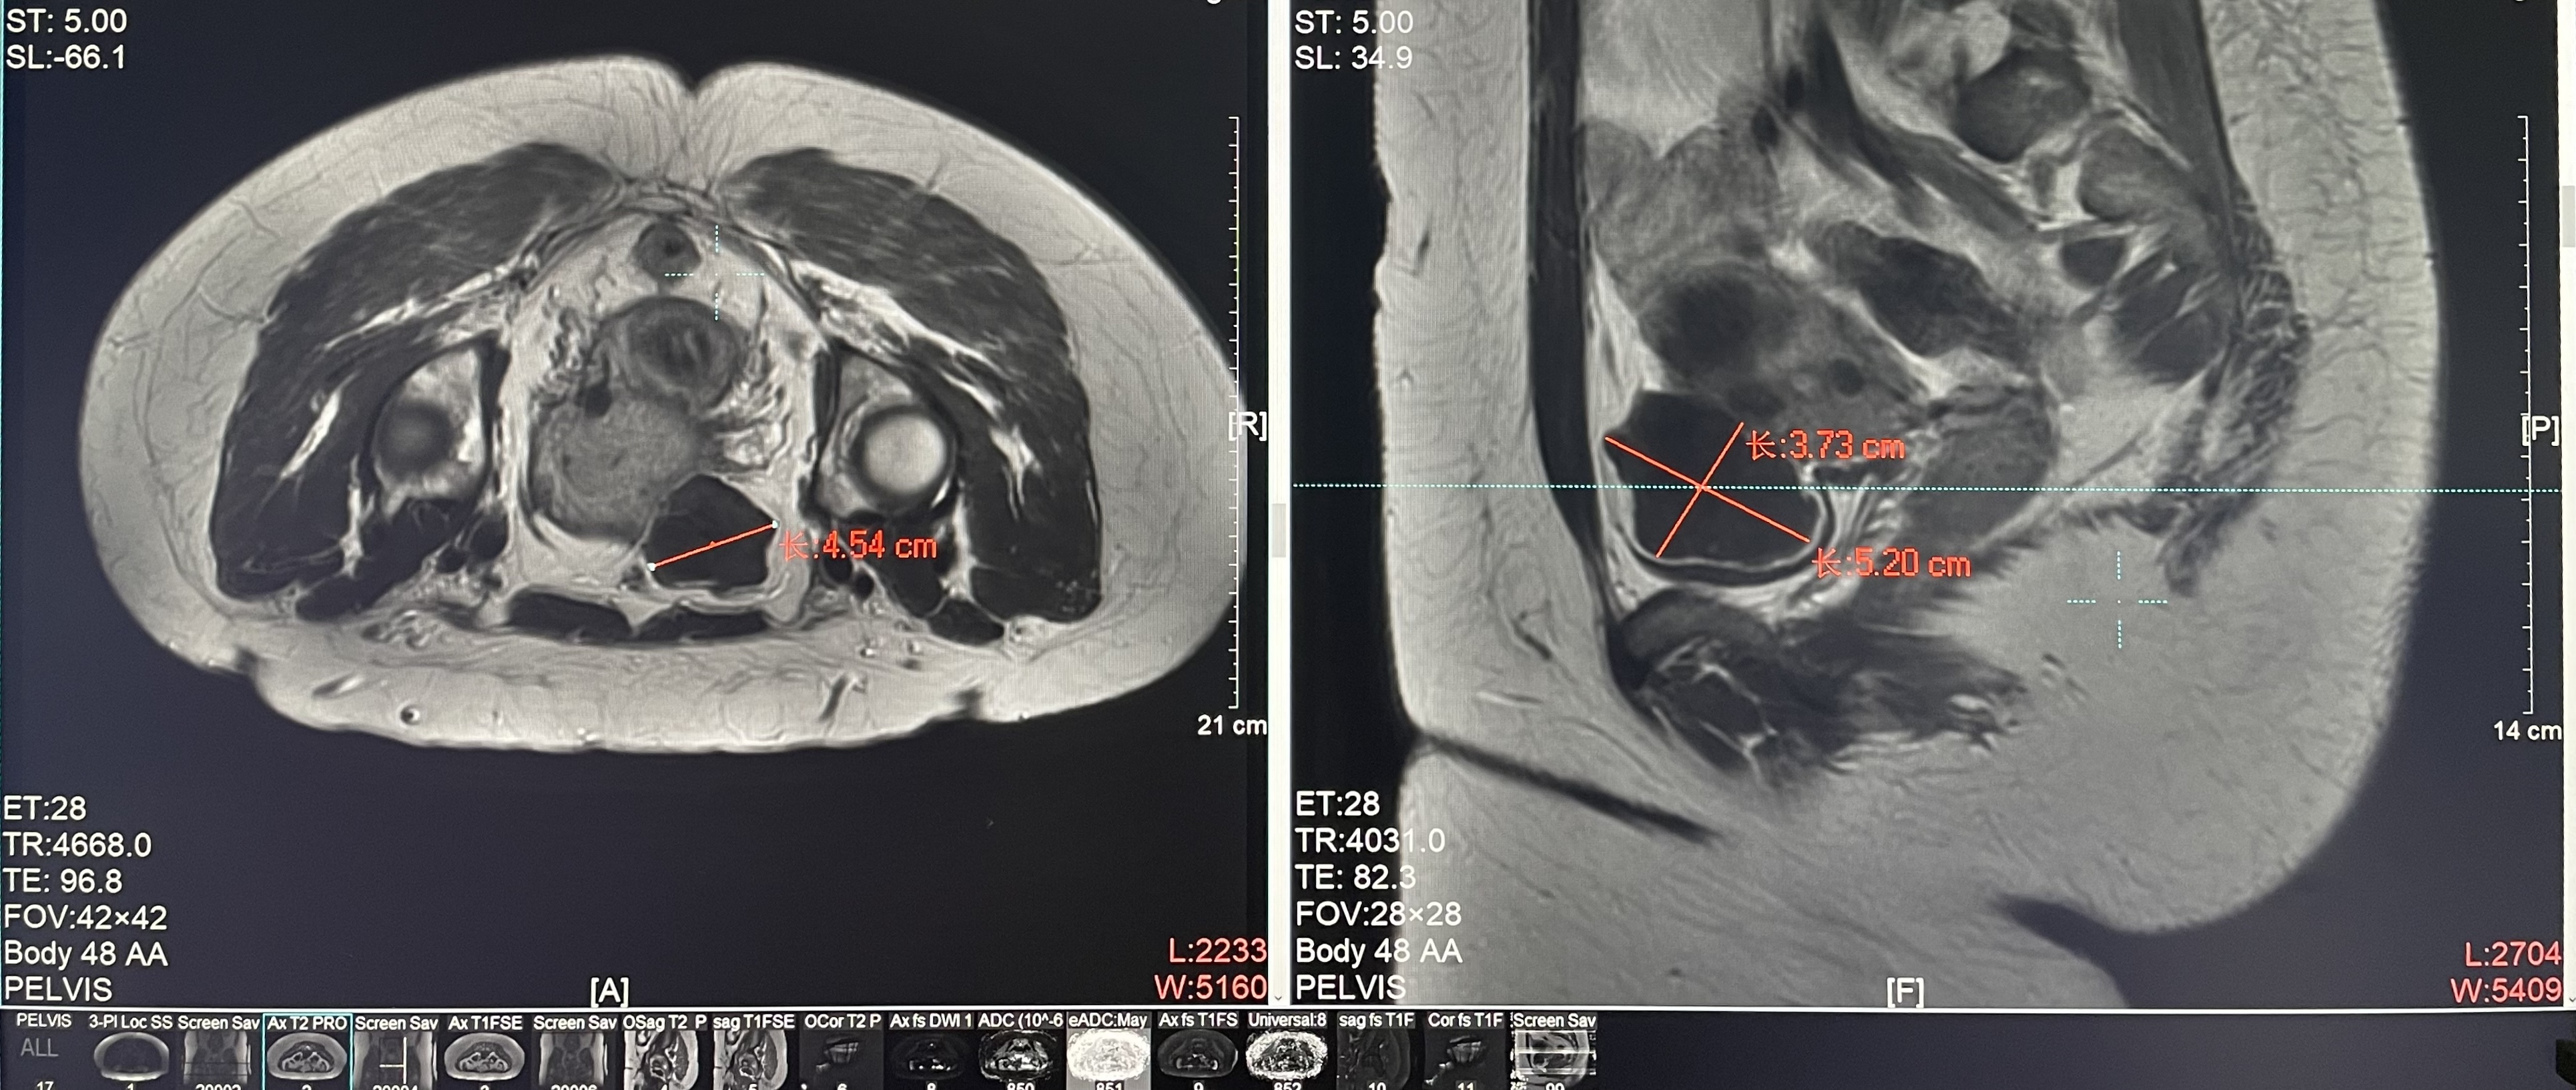

子宮肌瘤

患者信息:女,38

診斷:子宮肌瘤

腫瘤尺寸:約為45*52*38mm

ROT深度:腫瘤的ROT中心距離皮膚62mm

術后評估:術后造影增強圖像顯示消融區(qū)域(右側)與腫瘤區(qū)域(左側)重合度較好,非灌注區(qū)域連續(xù)且一致。

結論:對該腫瘤具有非常好的消融效果,治療過程中,溫度上升曲線符合預期,每個被治療的靶點240CEM區(qū)域體積較大、外形飽滿、連續(xù)。病灶消融良好,NPV體積比約88.7%。